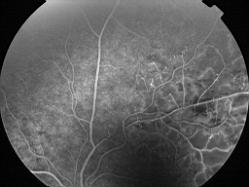

OCCLUSION DE BRANCHE DE LA VTS DE FORME ISCHEMIQUE MAJEURE